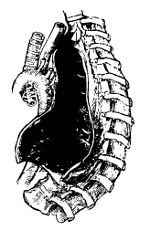

| Lumbar Abscess | 441 |